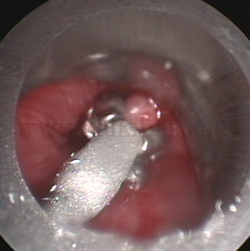

Cuerpo

extraño endobronquial |